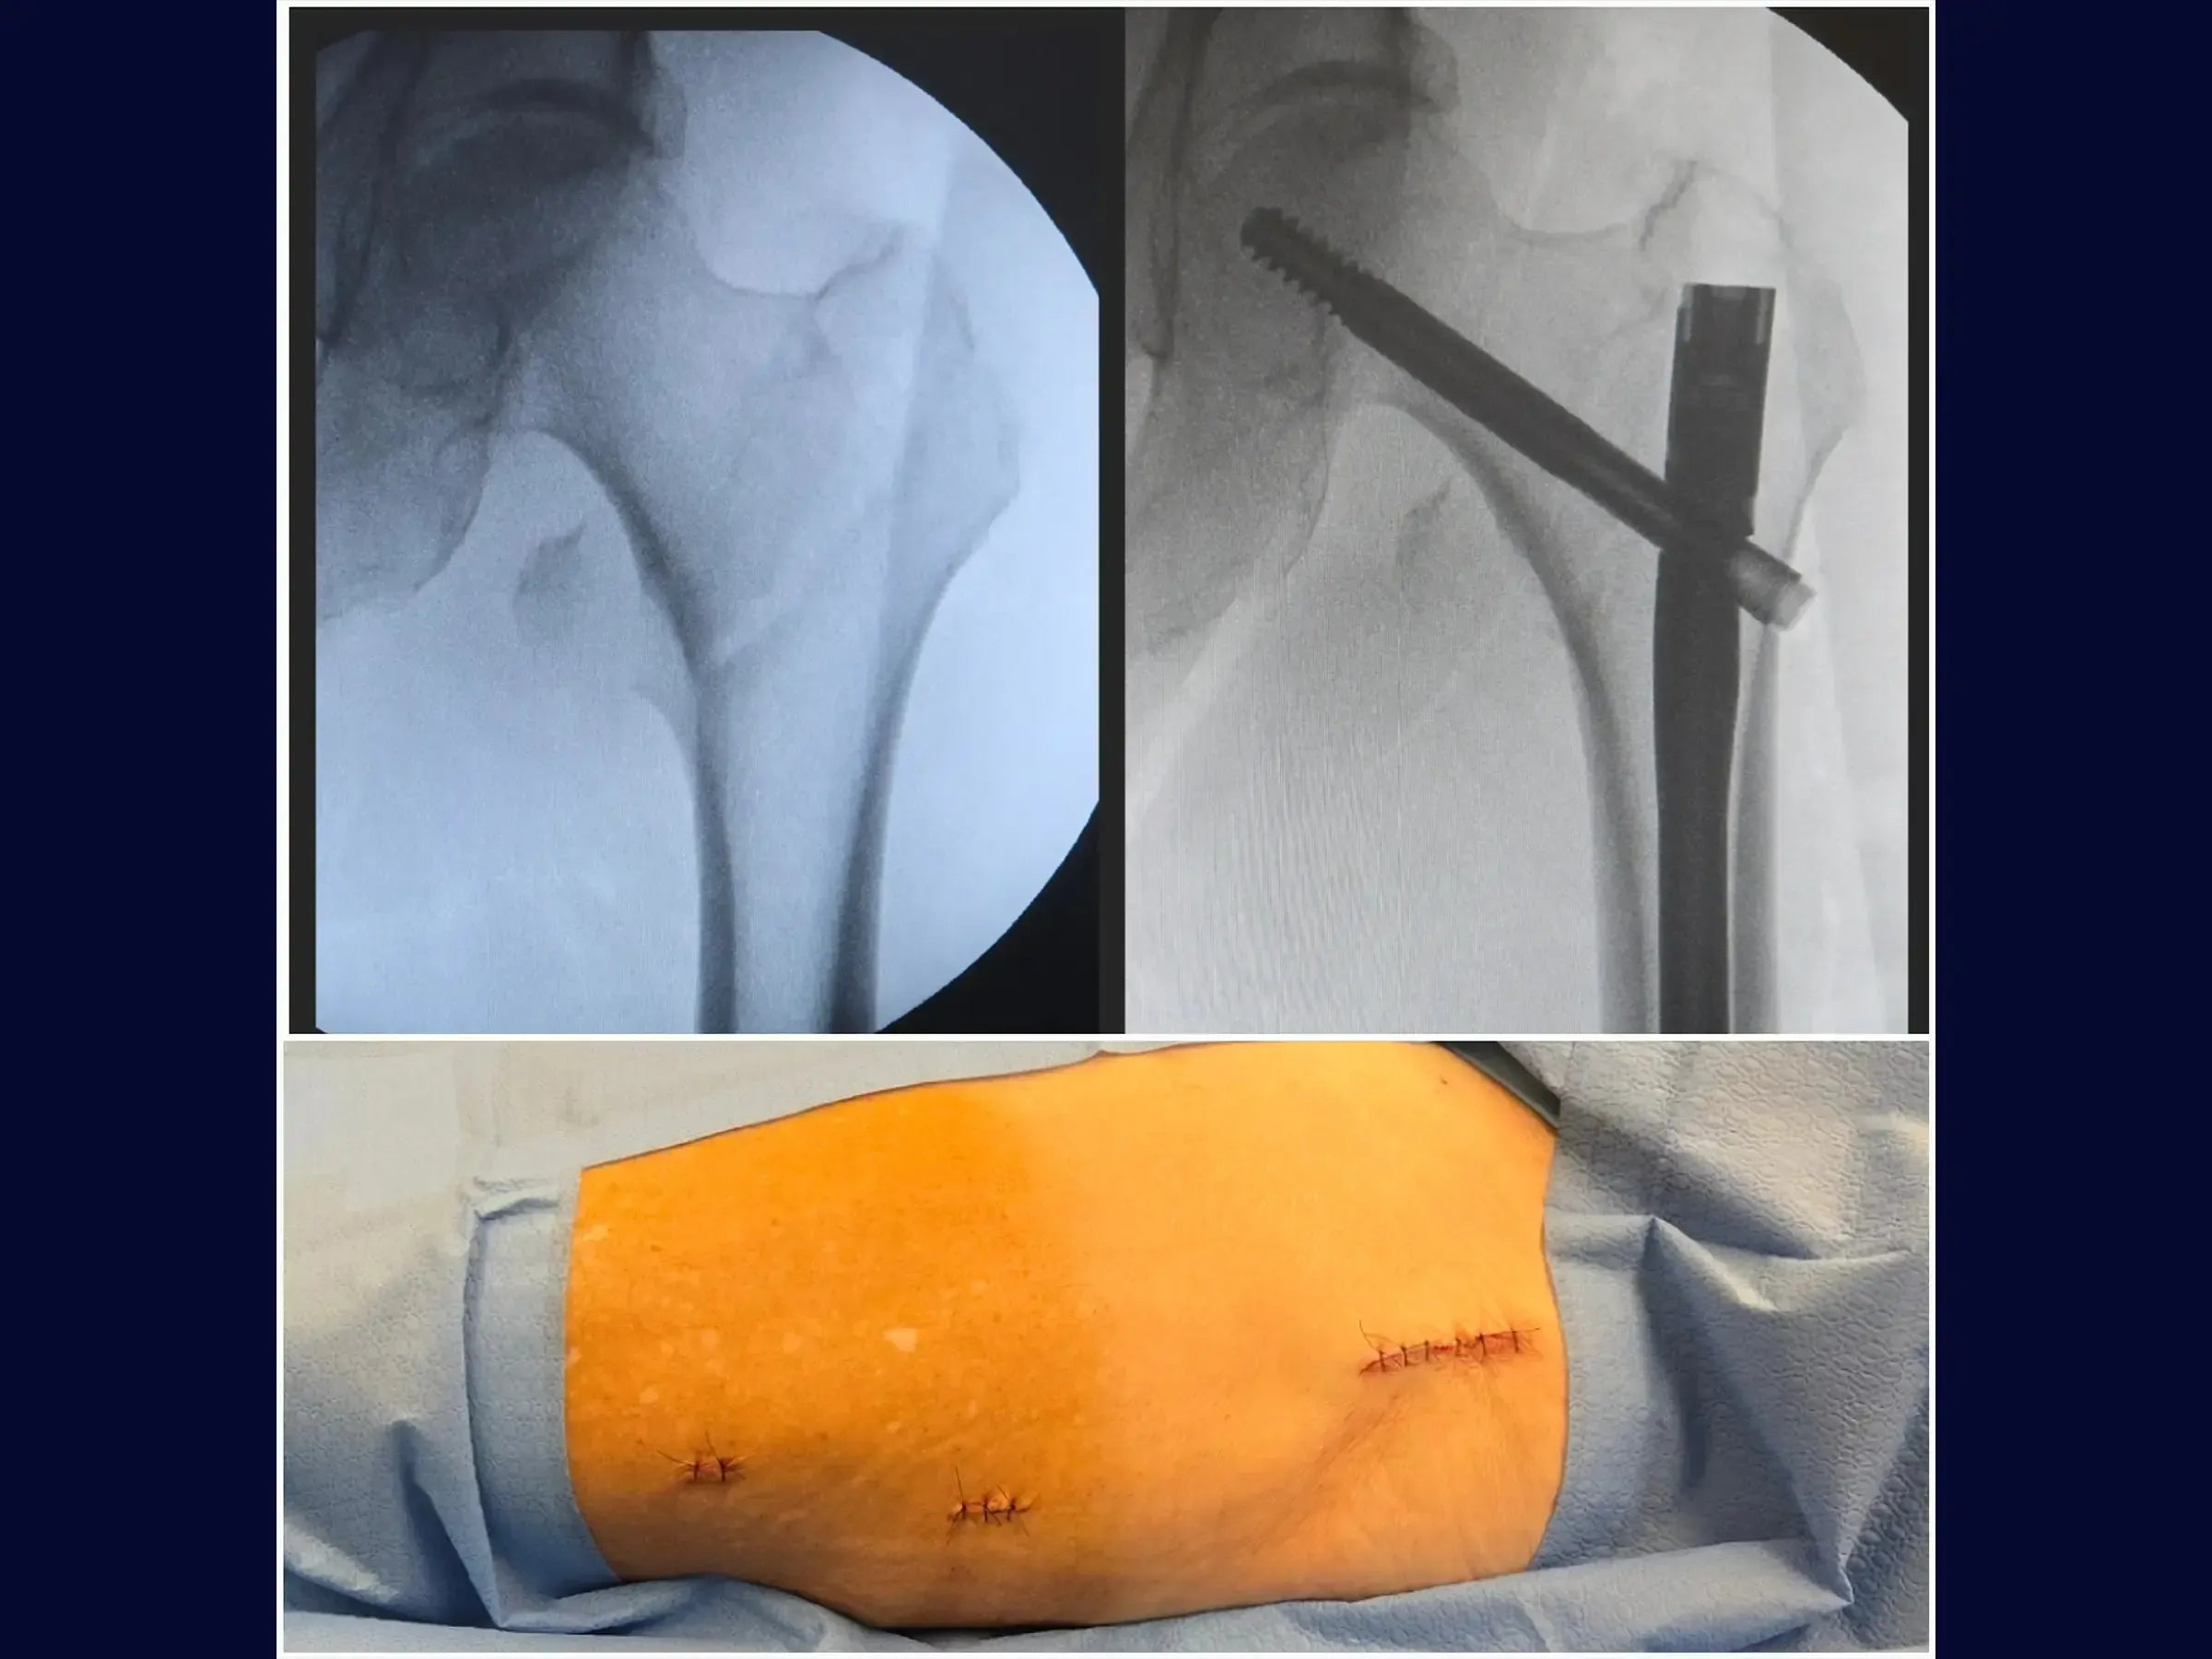

- Inserção de Parafusos: Faça uma abertura minimamente invasiva lateral para o fio guia do parafuso deslizante, confirmando seu direcionamento para o centro da cabeça do fêmur em ambas as vistas. Meça e insira o parafuso deslizante, usando um segundo fio guia para evitar seu retorno. O bloqueio distal é guiado pelo introdutor da haste, com incisão de 1.5 cm. Certifique-se de que o parafuso deslizante permita pistonamento.

- Resultados: A fratura é reduzida anatomicamente, com o implante bem posicionado. A cirurgia minimamente invasiva permite apoio de carga precoce para o paciente idoso.

- PDF Detalhado: Abrange desde o posicionamento e ponto de entrada do fio guia, otimização do posicionamento na visão lateral, abertura do canal medular, inserção da haste e parafuso deslizante, até o bloqueio distal e finalização. Também inclui um resumo prático com os pontos-chave da técnica.